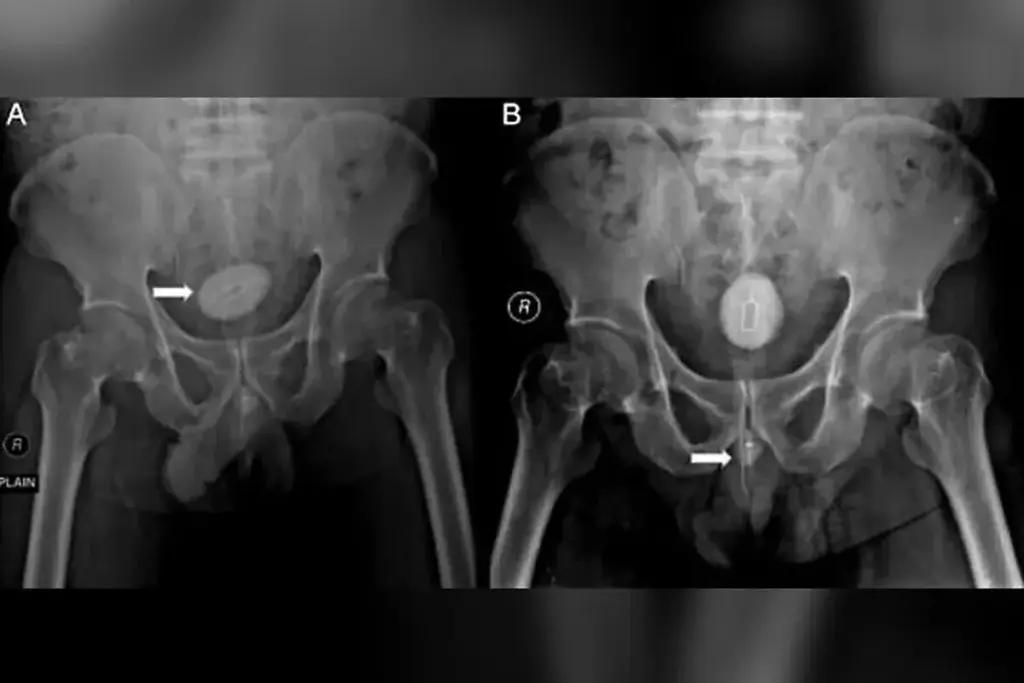

Other methods are used for urethral problems too. Retrograde urethrography (RUG) is the top choice for seeing the urethra. It involves putting contrast material into the urethra to show its inside.

RUG gives detailed views of the urethra, key for finding strictures. Ultrasound and MRI might also be used, based on the patient’s needs and the issue.

X-rays, like retrograde urethrography (RUG) and voiding cystourethrography (VCUG), are also used. They use contrast to see the urethra on X-rays. But they might not show soft tissue as well as MRI or CT scans.